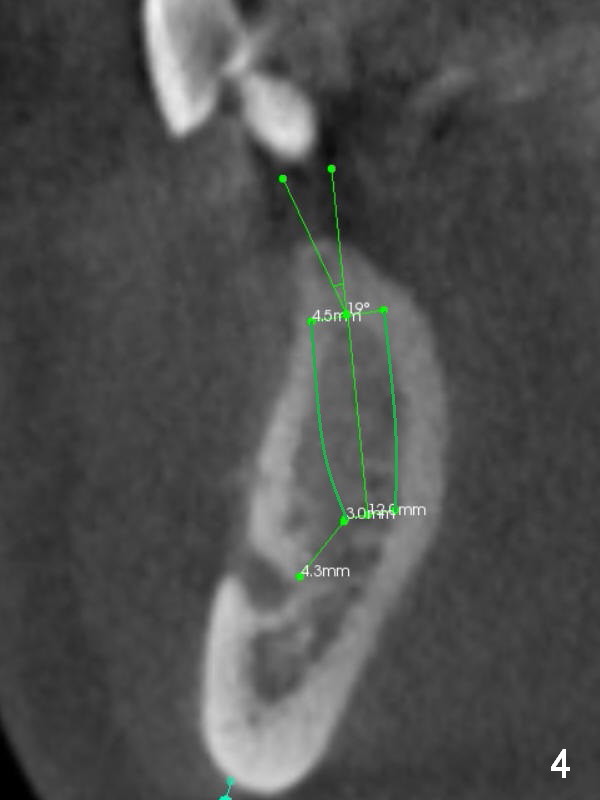

A 39-year-old man had an accident, which caused loss of several teeth 20 years ago. The patient (wearing removable partial dentures) decides to restore #28,29 with implants first (Fig.1 CBCT sagittal section). Coronal section at #28 shows narrow ridge coronally (Fig.2). To place an implant, the pointed ridge top has to be removed about 4.5 mm (Fig.3). Probably due to severe bone resorption post extraction, an angled abutment may be needed as much as 20 degree (Fig.4).